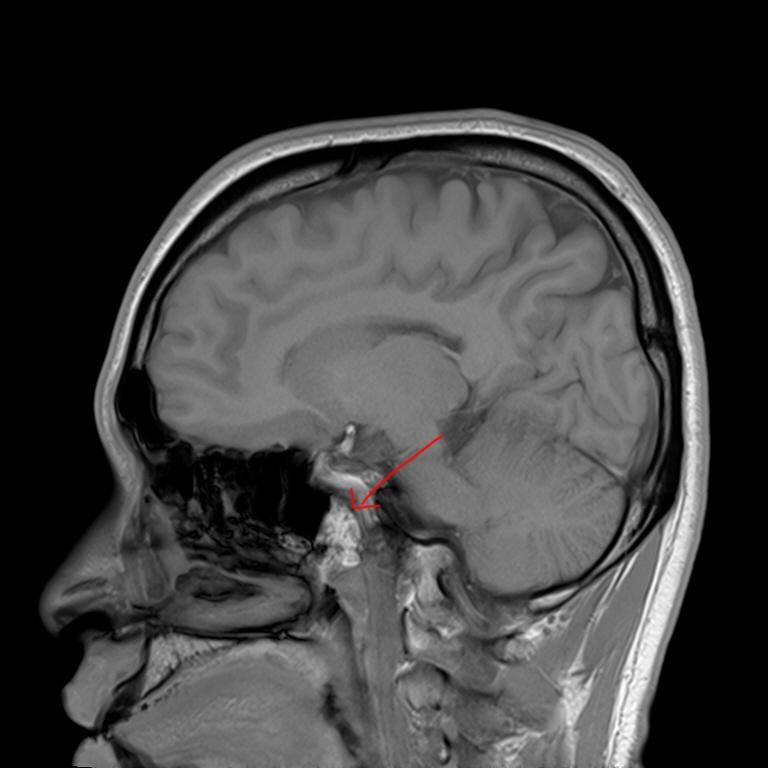

mri 사진을 봤을 때 정확히 어디가 막힌 걸까요? 그리고 치료는 할 수 있는 걸까요???

• 2번 째 사진

올려주신 영상 관련 보다 더 자세한 분석 원하시면 영상의학과 전문의한테 물어보셔야 해요

말씀하신 증상 관련 답변 드리자면 15년동안 지속된 귀와 코 사이 막힘 증상은 이관(유스타키오관) 기능 장애일 가능성이 높습니다. 진한 콧물을 강하게 들이마신 후부터 증상이 생겼다면, 이관이 분비물이나 압력 변화로 막히거나 손상되었을 가능성이 있습니다. 이관은 코 뒤쪽과 귀 중이를 연결하는 통로로, 막히면 귀먹먹함, 압력감, 울림 증상 등이 지속될 수 있습니다. MRI나 CT를 통해 이관 주변 구조(비인두, 부비동, 중이강 등)의 해부학적 이상을 더 정확히 확인해야 합니다.